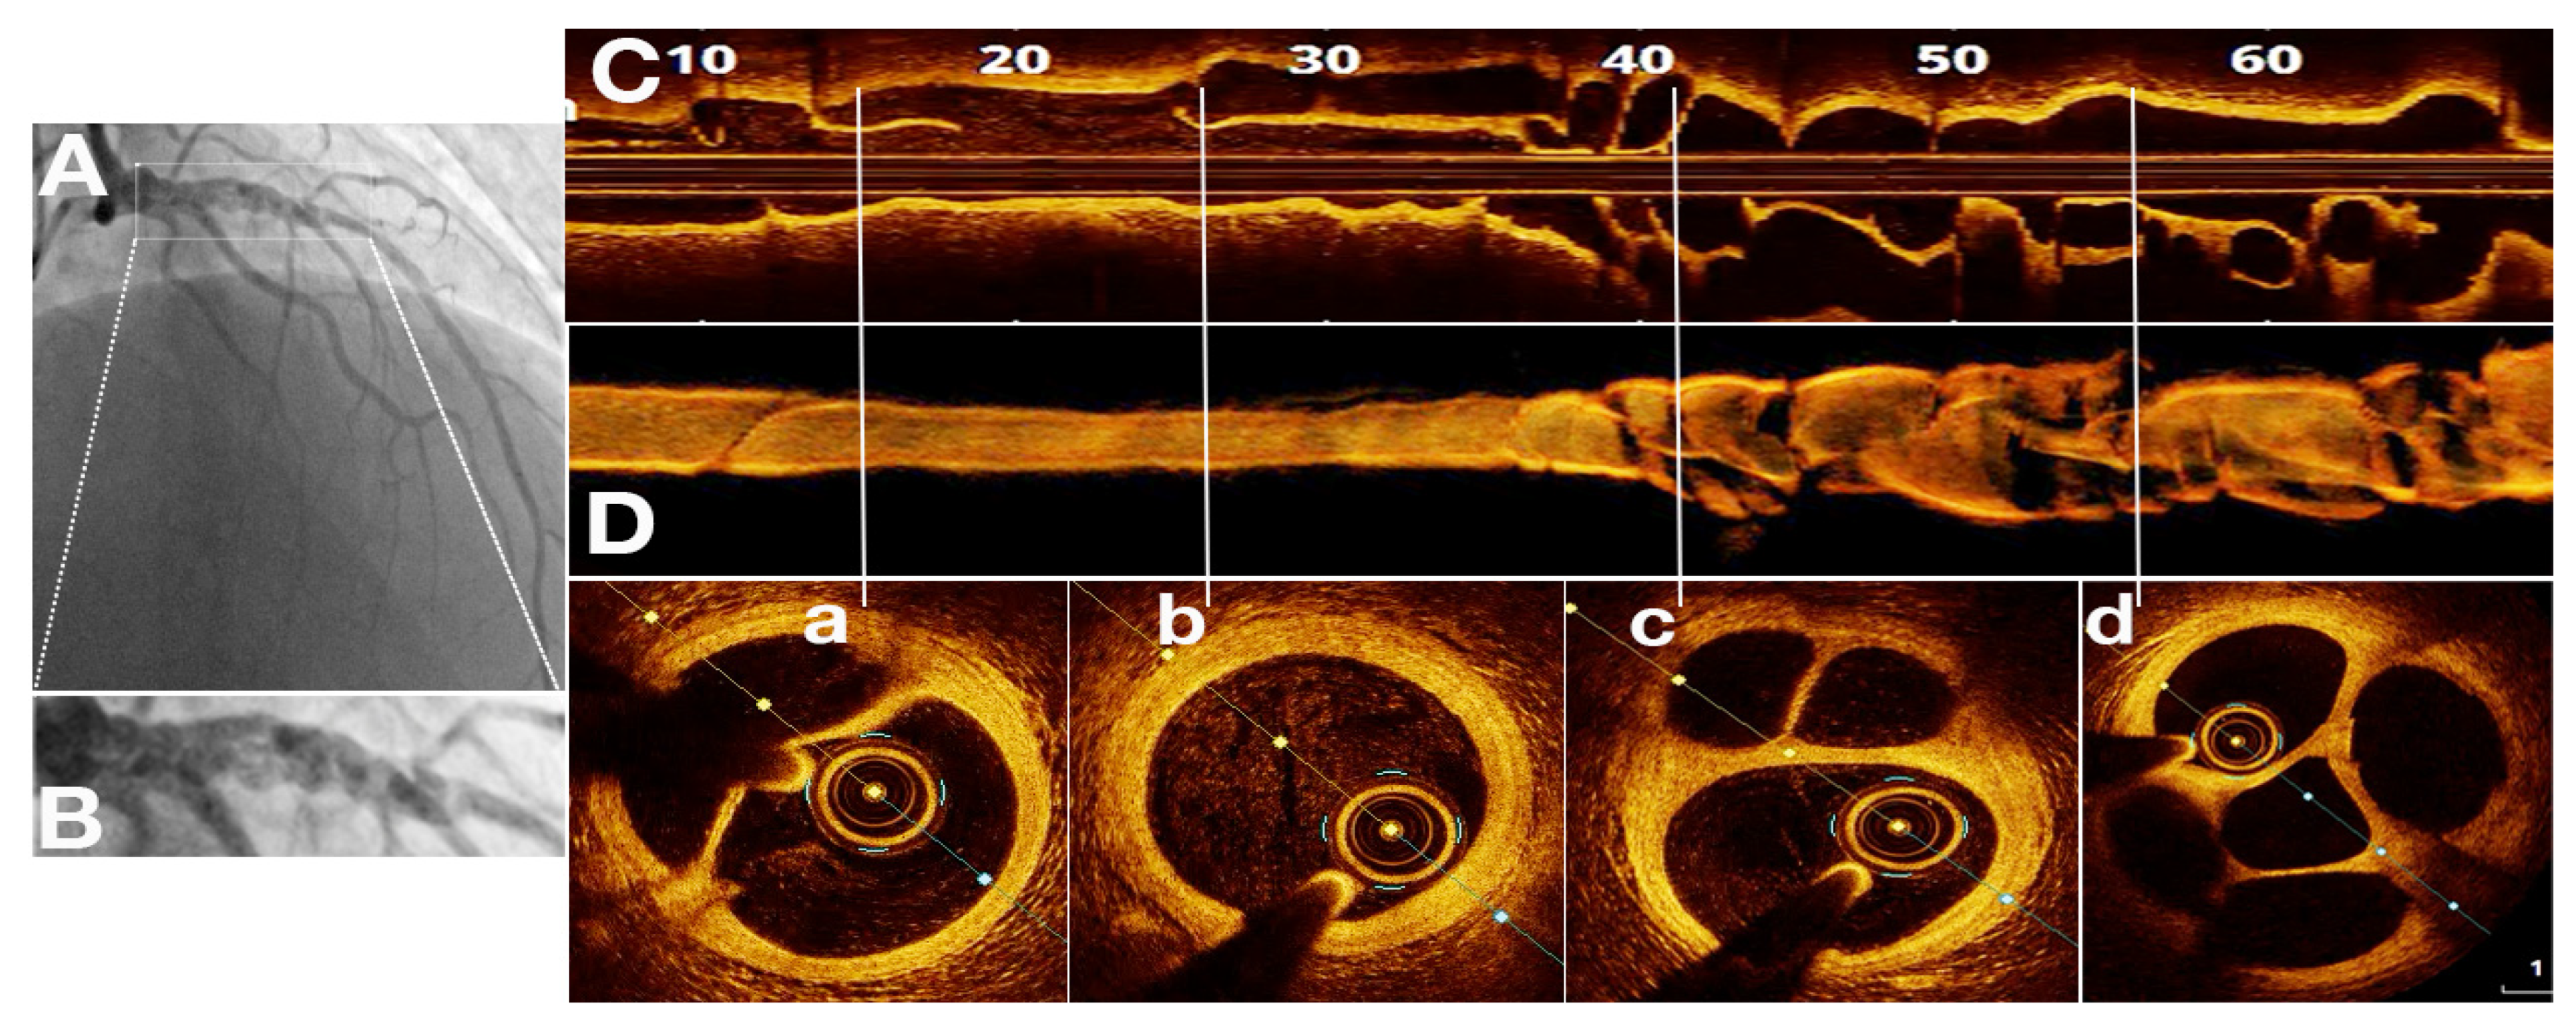

OCT in SRCT